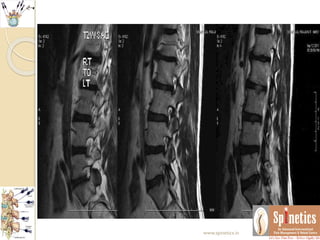

Unusual case

 A male 42 years had acute excruciating leg and back pain

 He was a hard worker laborer

 Financial issues

 Govt hospital resistance

 Subjected to pain management after lots of consents

 Within 24 hours, Injected transforaminal ozone after

confirmation with non ionic contrast

 Waited for few minutes till any untowards events to

occur

 With comfortable vital parameters, planning to shift him

in recovery area, rather he immidiately walk out pain free

 Even long term followup kept to see any reoccurance

 Neurological behaviour differs in same presenting

spine conditions

 Even though we repeated MRI in one month span as

there is no reccurance what it suggest

 There is resolving annular tear with sequestration

 Many of our patients we routinely found such

herniations which might be too painful to the

patients

 In opposite this patient was not having any

symptoms regarding reccurance of pain

 This the follow-up of more than 2and half years